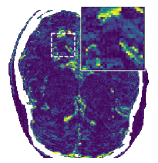

Figure 5 shows an example of a spatio-temporal regularization parameter-map which was estimated using the proposed approach for an acceleration factor of . The network estimates the regularization parameter-map to be pointwise relatively consistenly higher than the spatially required regularization. This result is in fact expected as the temporal dimension is the one for which the gradients of the images are the sparsest because of the high temporal correlation. Further, we see how the network consistently predicts both the spatial regularization as well as the temporal regularization to be less strong in the area where most of the movement is expected, i.e. in the cardiac region.

Figure 6 shows examples of the quantitative (magnitude) images of three of the 112 simulated inversion recovery measurements in the test dataset. We also show the regularization parameter-maps for regularization along the spatial directions and along the inversion-time direction generated by the network. The mean PSNR and SSIM of our proposed method is consistently higher for all considered acceleration factors, even compared to PDHG with regularization strength along spatial and inversion-time direction chosen by grid-search with access to the ground truth images (shown in Figure 8 and Table 2). The resulting parameter-maps after performing the regression on the reconstructed images are shown in Figure 7. Again, our proposed method results in the lowest RMS deviation from the ground truth images (Table 2).